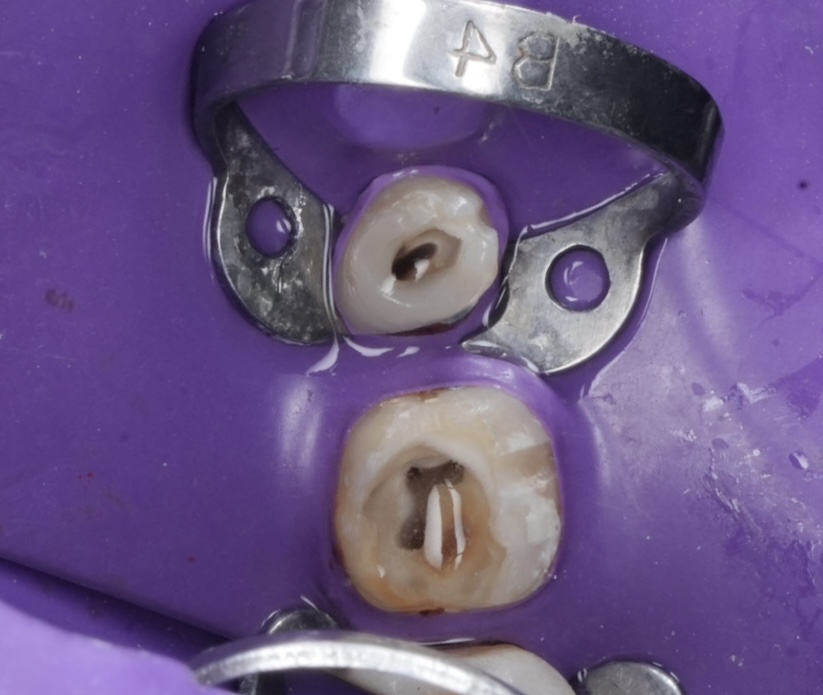

4. Obturation

Obturation performed with Bioceramic Sealer (Endo Sequence BC) and warm vertical condensation to ensure apical seal and coronal adaptation (Fig 3).

Radiograph confirmed ideal obturation, core adaptation, and marginal integrity (Fig 3). The final restoration blended esthetically and functionally with the dentition (Fig 5).

- Fig 3: Post-obturation radiograph confirming dense 3-D fill.